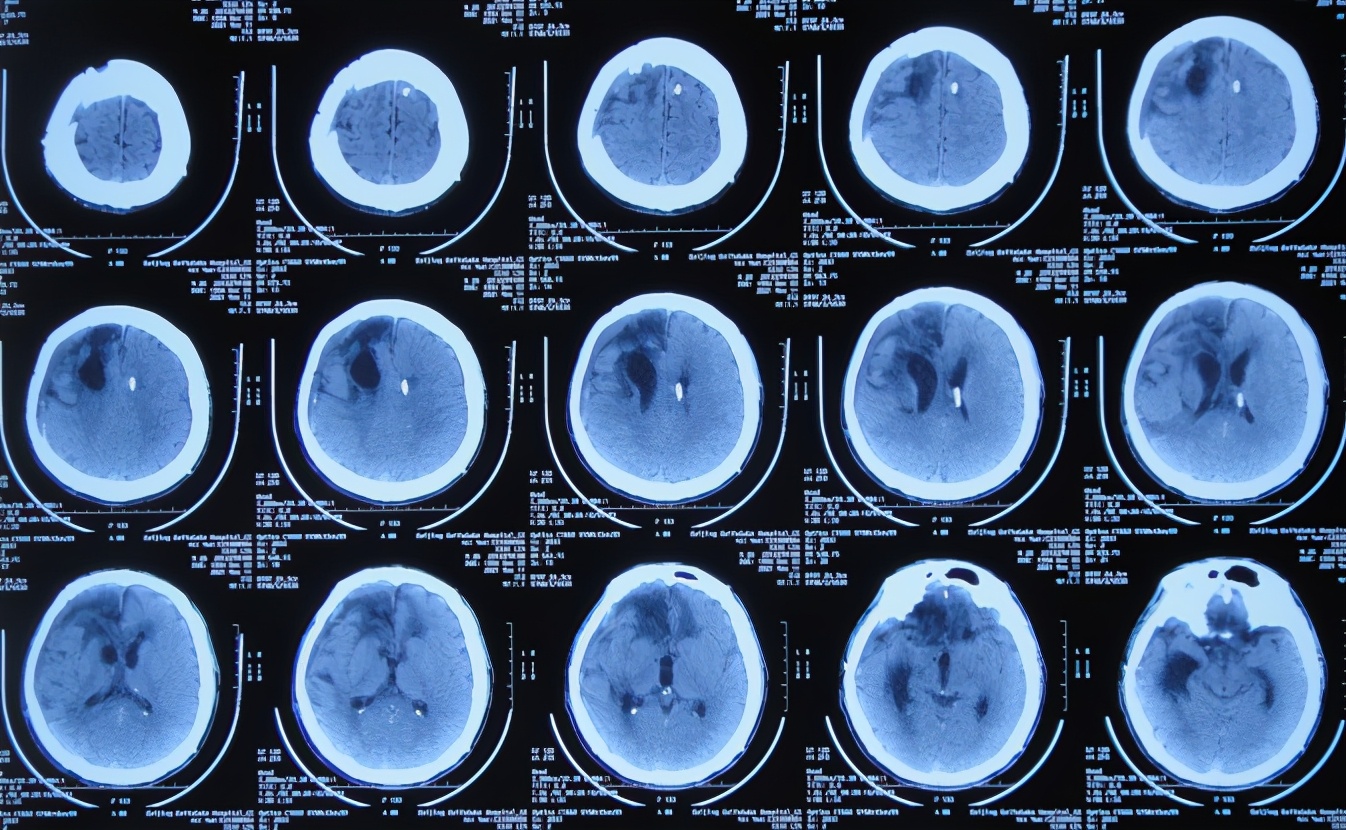

开颅术后9天即2020年12月21日,查头颅CT示有好转( 图-4 )。

图-4: 2020年12月21日头颅CT

开颅术后10天即2020年12月22日(腰大池引流6天后),腰大池引流期间无发热,因脑脊液颜色血色转为黄色,给予拔除腰大池引流管;但查头颅CT示仍有脑膨出,且脑室有稍增大( 图-5 ),肺部CT认为有点感染( 图-6 )。

图-5: 2020年12月22日头颅CT